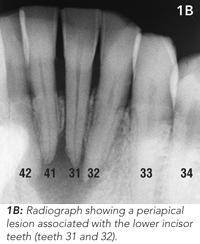

Routine clinical dental tests were conducted, including tooth percussion and CO2 dental pulp testing. Radiographic examination revealed a broad radiolucency associated with three of the lower incisor teeth (Figure 1B). These findings led to a diagnosis of chronic apical periodontitis caused by pulpal necrosis and infection of two lower incisor teeth (teeth 31 and 32). Tooth 41 was vital.